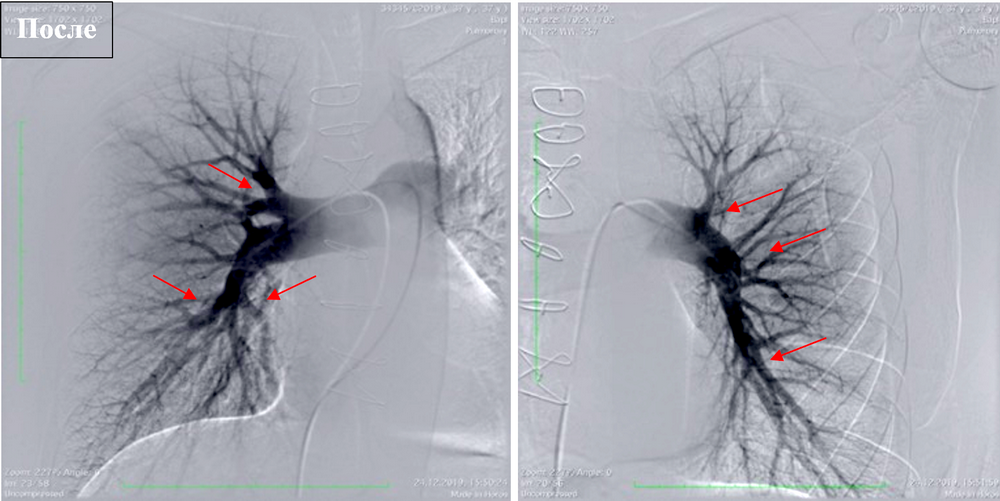

Сравнение данных ангиопульмонографии до и после операции (тромбэндартерэктомия из легочной артерии) |